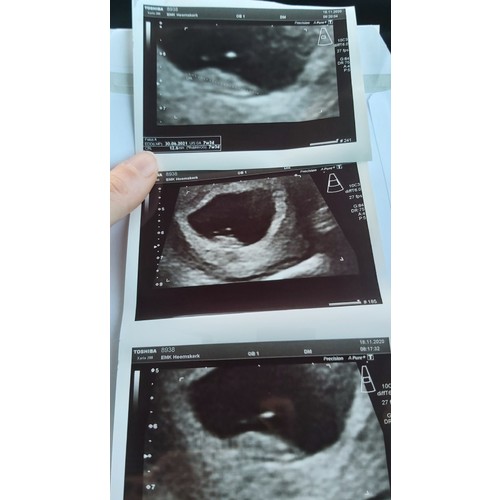

Ik dacht 8 weken te zijn bij de echo ze hadden me alleen iets terug gezet naar 7+4. Nu alweer een goede termijn echo gehad en vandaag alweer 11+4.

Ligt een beetje aan de verloskundige waar je zit. Bij de verloskundige waar ik bij zit is dit een medische echo. De vitaliteits echo. Waar ze kijken of er een gezonde zwangerschap is en of het een een of een meerling is. Dit doen ze vaak tussen de 7 en 9 weken.

Helaas moeilijk tezien gisteren echo gehad ban 8+5 maar mijn baarmoeder ligt nog wat verder naar achter dus niet zn hele helderen echo maar hartje klopt en alles was goed 😍😍